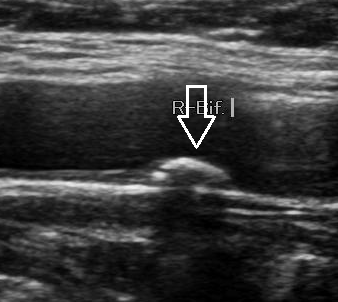

- 젤을 바른 후 초음파 탐촉자를 경동맥 위에 대고 영상 관찰

- 혈류 속도 측정과 플라크 유무 확인